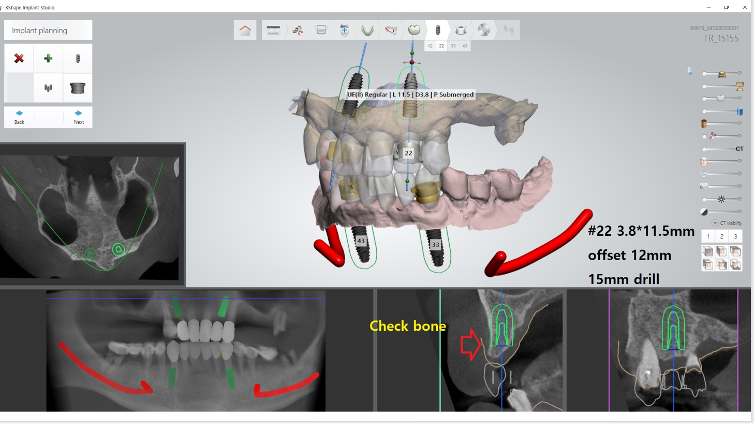

Yüksek riskli vakalarda cerrahi süreyi kısaltmak ve doku travmasını minimumda tutmak hayati önem taşır. Bu nedenle, tamamen Guided (Rehberli) Cerrahi yolunu seçtim. Dijital planlama sayesinde, milimetrik hassasiyetle çalışarak enfeksiyon riskini ve operasyon sonrası ödemi minimize etmeyi hedefledim. Kesik yok, dikiş yok, enfeksiyon riski az.

Bu vakada, implant yüzeyinin kemikle olan biyolojik etkileşimini en üst seviyeye çıkarmak için UV Active (fotofonksiyonel) implantlar kullandım. UV ışını ile aktive edilen bu implant yüzeyleri, diyabet gibi iyileşmenin yavaş olduğu durumlarda kemik hücrelerinin implanta çok daha hızlı ve güçlü tutunmasını sağlar. Alt ve üst çeneye rehberli cerrahiyle yerleştirdiğim bu implantları, Locator tutucularla destekleyerek hastamız için hem güvenli hem de yeterince stabil bir hareketli protez altyapısı kurdum. Hastayı yaklaşık 5 yıldır takip ediyorum, herhangi bir problemi olmadan dişlerini sağlıkla kullanıyor.

Klinik Not: Hekimlikte başarı, hastanın sistemik risklerine uygun teknolojiyi doğru yerde kullanmaktır. HbA1c seviyesi 10 olan bu vakada; dijital planlamanın (Guided) getirdiği cerrahi doğruluk ile UV Active teknolojisinin sunduğu biyolojik hızı birleştirdim. Sonuç; diyabetik risklerin başarıyla yönetildiği, konforlu bir iyileşme süreci ve hastamızın yaşam kalitesine geri kazandırılan bir fonksiyon oldu.